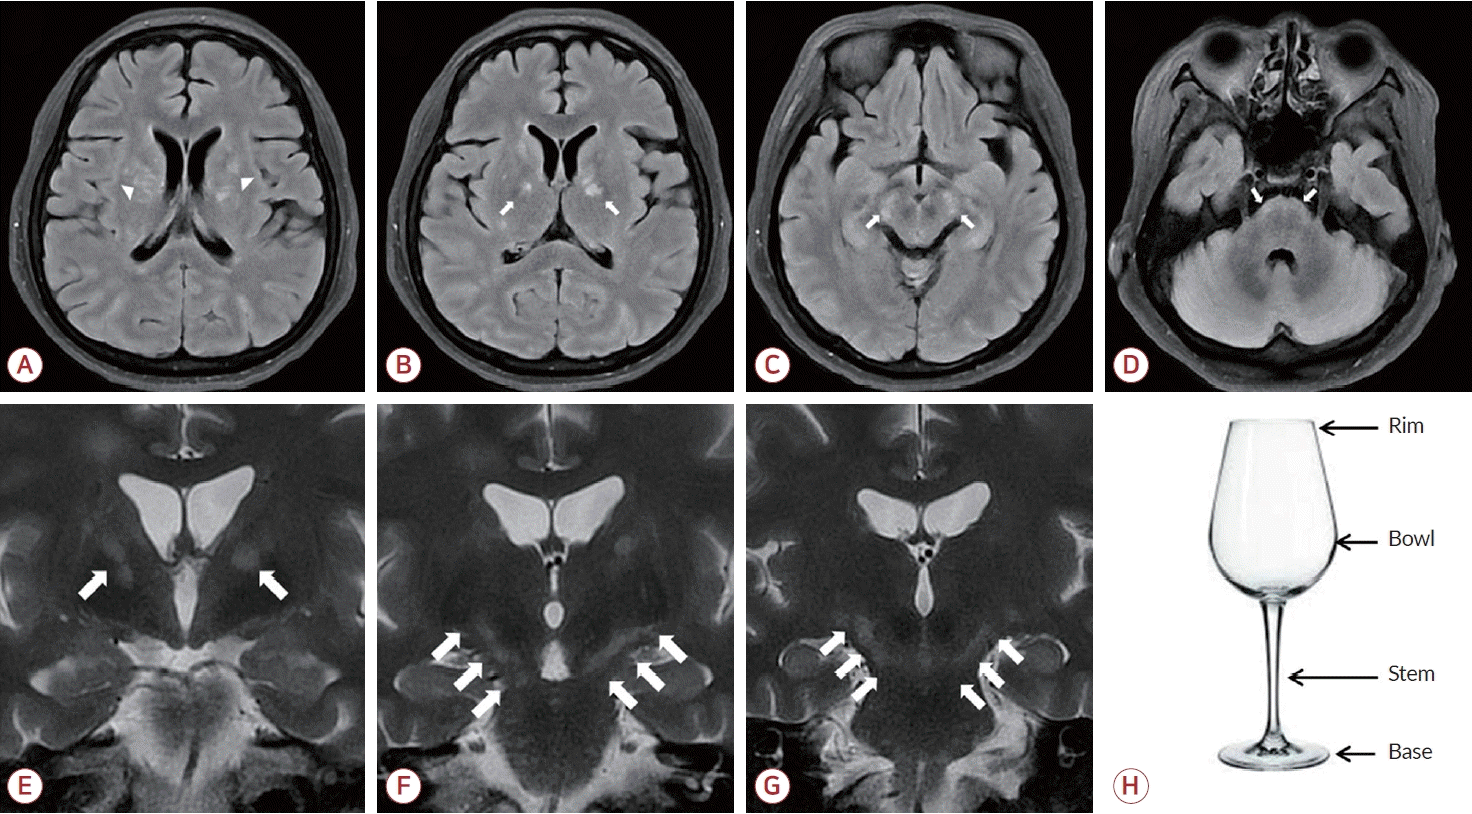

Figure 2.

Brain MRI at admission day 24. (A) Bilateral basal ganglia lesions (arrowheads) on FLAIR image. (B-D) Bilateral corticospinal tract lesions (arrows) on FLAIR images. (E-G) Bilateral corticospinal tract lesions (arrows) on coronal T2-weighted images. (H) Wine glass image. The lesions along the bilateral corticospinal tracts (E-G) resemble the outline of a wine glass. MRI; magnetic resonance imaging, FLAIR; fluid attenuated inversion recovery.

본 증례에서 환자는 임상적으로 두통과 발열, 의식 저하가 발생하였으며 과호흡으로 인한 호흡부전이 동반되었다. 뇌 MRI에서 양측 두정-후두엽의 피질 부종과 우측 전두엽백질에서 T2 고신호강도 병터뿐만 아니라 양측 피질척수로를 따라 여러 개의 고신호강도 병터가 확인되어 이전에 잘 보고되지 않았던 EBV뇌염의 영상 소견으로 생각된다. EBV뇌염의 뇌 MRI 영상 소견은 T2 강조영상에서 주로 두정-후두엽 피질, 피질하백질, 깊은회색질핵에 병터가 나타나며 대부분 가역적으로 회복된다고 알려져 있다[3-5]. 그 외에도 뇌줄기의 병터가 보고된 바 있으나 본 증례와 같이 양측의 피질척수로를 따라 발생한 병터를 보고한 증례는 없는 것으로 보인다. 뇌MRI의 T2 강조영상 혹은 FLAIR 영상의 관상단면에서 양측 피질척수로를 따라 고강도신호가 관찰되는 경우 포도주잔 그릇(bowl)의 선과 유사하다고 하여 포도주잔징후(wine glass sign)라 부르며 근위축측삭경화증이나 삼투수초용해(osmotic myelinolysis), 중추 신경계림프종에서 보고된 바 있다(Fig. 2-E-G, Table) [6].신경친화바이러스인 EBV가 뇌염을 발생시키는 기전은 중추 신경계로 직접 침범하거나 항체 매개 감염 후 염증반응을 통해 일으킨다[1,2]. 대부분의 경우 잠복 감염된 B세포에서 재활성화된 바이러스가 혈액뇌장벽을 통과하여 뇌염을 발생시키는 것으로 알려져 있다[2]. EBV는 B세포를 통한 이동 또는 뇌미세혈관 내피세포 감염을 통해 뇌에 침입하며 염증사이토카인, 바이러스 단백질의 방출과 T세포 매개반응을 통해 신경독성을 일으킨다. 또한 항체 매개 감염 후 염증반응은 EBV와 중추신경계 펩타이드 사이의 유사성으로 인해 T세포와 B세포가 교차 활성화되는 분자 모방(molecular mimicry)이 EBV의 중추신경계 병인으로 추정된다[7]. 이전에 보고된 증례들에서 EBV가 양측 피질하백질과 함께 바닥핵, 시상의 깊은회색질핵을 침범한 것을 확인할 수 있었으나 해당 부위에서 호발하는 기전에 대해서는 추가적인 연구가 필요하다.특히 본 증례에서는 특징적으로 뇌MRI에서 양측 피질척수로를 침범하여 포도주잔징후를 보였는데 유사한 소견을 보일 수 있는 질환들에 대한 감별이 필요하였다(Table). 뇌 병터를 시사하는 질환에 대한 가족력이 없었고 발열 및 감염과 관련된 징후와 증상을 동반하였으며 비교적 급성으로 진행하는 임상 경과를 보였기 때문에 감염, 유전 또는 신경퇴행질환의 가능성은 적었다. 또한 입원 시 신속 코로나항원 검사에서 음성이었으며 최근 백신을 접종받은 병력 또한 없었다. 시신경척수염과 같은 탈수초질환에서는 지속되는 발열을 동반하지 않으며 환자에서는 특징적인 시신경 혹은 척수 병터가 없었고 진단항체 검사에서 모두 음성이 나와 배제하였다. 감염질환에 대한 검사 중 뇌척수액 검사에서 EBV에 대한 PCR이 양성으로 확인되어 EBV뇌염으로 진단하였다. 또한 추적 관찰을 위해 시행한 뇌 MRI에서 뇌실질의 새로운 미세출혈들이 발견되었는데 이는 EBV뇌염에서 동반될 수 있는 부종출혈 또는 혈관염으로 판단하였다[8,9].또한 발병 초기에 증상이 진행하면서 과호흡이 동반되었고 점차 악화되어 호흡부전으로 진행하여 기계호흡을 적용하게 되었다. 뇌압 조절을 위해 투여했던 아세타졸아미드가 유발한 대사산증이 원인일 수도 있지만 호흡알칼리증이 선행된 것으로 보이며 젖산의 상승이 없었던 점을 고려하여 아세타졸아미드에 의한 과호흡 유발은 다소 가능성이 낮을 것으로 생각하였다. 따라서 뇌염에 의한 뇌줄기의 중간뇌와 다리뇌의 손상으로 인한 중추과호흡에 의한 증상으로 추정하였다[10].본 증례의 환자는 두통, 발열로 병원에 와서 항바이러스제로 치료하였으나 점차 의식 저하, 호흡부전이 발생하여 기계 호흡 및 기관절개술을 시행하였으며 증상이 호전되어 퇴원 후 외래에서 추적 관찰 중이다. 혈액 및 뇌척수액 PCR에서는 EBV가 검출되었고 입원 24일째 시행한 뇌MRI에서 양측 피질척수로를 따라 이어지는 병터를 확인할 수 있었다. 영상 검사에서 양측 피질척수로를 침범하여 포도주잔징후를 시사하는 병터가 있는 경우 다양한 병인을 고려하여 감별 진단을 할 필요가 있으며 본 증례처럼 EBV뇌염도 고려하는 것이 필요하겠다.